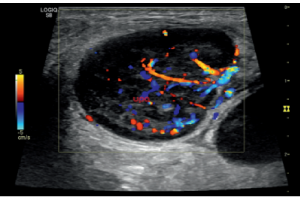

- Система Logiq S8 GE Healtcare, производства Россия – это уникальная ультразвуковая система экспертного класса, компактная и мобильная, удобная в эксплуатации.

- B-режим, M-режим, PW допплер, цветовое допплеровское картирование и энергетический допплер, кодированное излучение, кодированную тканевую гармонику.

- Программа 3D реконструкции для цветового допплеровского картирования и энергетического допплера: